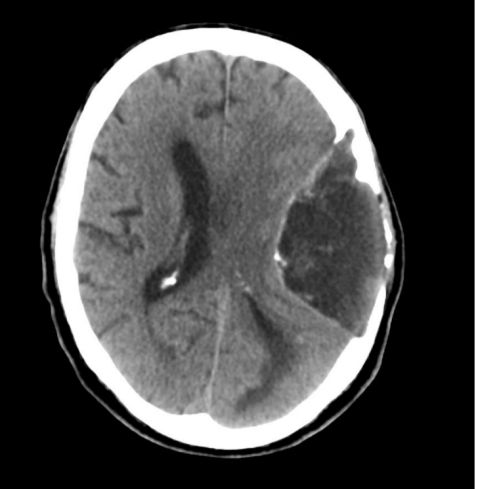

4 月前 CT 如图,本次复查 CT 无明显变化。既往史有高血压和抑郁症。怎么诊断?

患者 4 月前 CT提示颅内左侧顶部有 9cm×7.5cm 低密度肿块,周围颅盖变薄,中线轻度右移。本次入院复查 CT 无明显变化,但 CT 结果无法明确「表皮样囊肿」还是「皮样囊肿」,